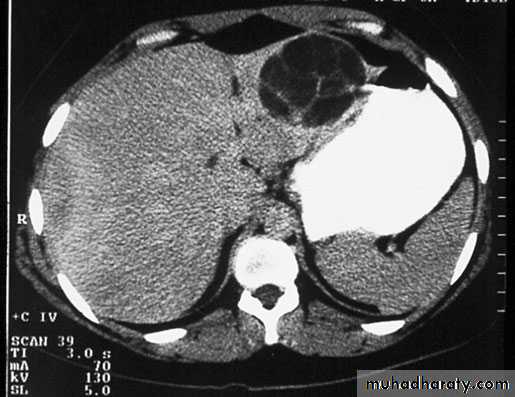

Ultrasound and CT scan are the investigations of choice. The CT scan shows a smooth space-occupying lesion with several septa .An ultrasound of the biliary tract may show abnormality in thegall bladder and bile ducts. Hydatid infestation of the biliary system should then be suspected.